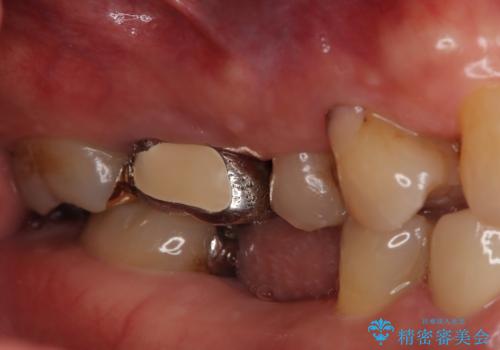

- 定期的に本院に通院されている患者様で、前歯の揺れがあると相談されました。下の奥歯が左右合わせて3本喪失されており、噛み合わせの負担が前歯にも集中していることを説明しました。右下6番の歯に関しては、事前の診査で十分な骨量がありましたのでインプラントを1本埋入しました。左下5番・6番にも本来はインプラントを埋入したかったのですが、骨量が十分でなく、骨を増やす処置をすると神経が近くリスクがあることから、審美性に配慮した金属のばねが見えないノンクラスプデンチャーを製作しました。また、このとき入れ歯を支える左下7番に根尖病変がありましたので、根管治療も行っております。(根管治療は当院院長で専門医を持つDr.林が担当しています。)治療終了後、約1年が経過しましたが、問題なく経過しており患者様も喜ばれていました。